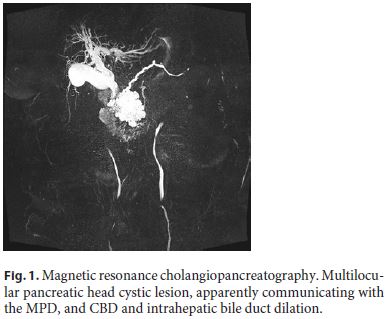

Magnetic resonance cholangiopancreatography showed a multilocular pancreatic head cystic lesion, measuring 60 × 70 × 57 mm and apparently communicating with the main pancreatic duct (MPD), without evident central scar. There was also CBD and intrahepatic bile duct dilation, as well as pancreatic body and tail atrophy (Fig. 1).